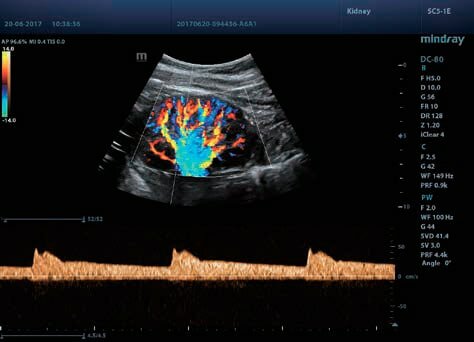

Клинические изображения

- Smart Track - функция позволяет уменьшить повторяющиеся и длительные шаги сканирования в сосудистых экзаменах, обеспечивает интеллектуальное отслеживание сосудов в реальном времени и оптимизацию изображений в реальном времени Color и PW.

- Smart Track - функция позволяет уменьшить повторяющиеся и длительные шаги сканирования в сосудистых экзаменах, обеспечивает интеллектуальное отслеживание сосудов в реальном времени и оптимизацию изображений в реальном времени Color и PW.

- Smart Track – уникальная методика для визуализации сосудов в PWD/CDI-режимах.